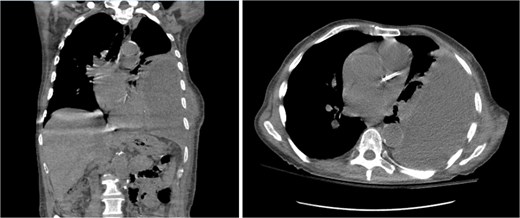

On presentation, chest radiography (Fig. 1) showed a large loculated left pleural effusion, and computed tomography (CT) scan (Fig. 2) confirmed the presence of the effusion with extension into the chest wall. The patient appeared ill with increased work of breathing. Physical exam revealed a large, fluctuant area with a solid component superior to the previous chest tube site, with no overlying skin changes. Blood work was significant for hyponatremia to 127 and a white blood cell count of 10.3 with no neutrophilic predominance. The patient was admitted, started on IV antibiotics, and dual antiplatelet therapy was held in preparation of surgical treatment of his EN. During this time, the fluctuant mass developed an opening, creating a pleurocutaneous fistula, and began to drain significant purulent fluid, which was sent for bacterial cultures.

Coronal (left) and axial (right) view CT scan of the chest showing a large complex loculated left pleural effusion with bulging into the chest wall, raising concern for empyema necessitans.